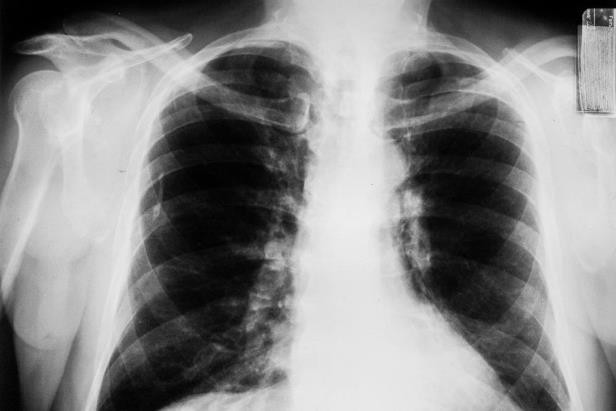

15/09/2018 14:34Người phụ nữ này bị ung thư phổi ở tuổi 31, nguyên nhân do chính thứ 'ẩn nấp' trong nhà mà không ai nhìn thấy

31 tuổi đã bị ung thư phổi dù không hút thuốc và chăm tập thể dục

Khi cơn đau ở nách không đỡ, cô biết rằng cô cần nghiêm túc để ý đến tình trạng của mình. Bác sĩ sản khoa đã từ chối chụp MRI vú (chụp cộng hưởng từ) cho cô. Malmberg đã bay tới Michigan để được khám với một bác sĩ khác. "Ngực của tôi trông khỏe mạnh nhưng họ lại tìm thấy một khối u trên phổi của tôi. Trong ngày hôm đó, tôi đã chụp CT. Thực tế, tôi còn trẻ, lại không có triệu chứng ung thư nên bác sĩ nghĩ có thể tôi bị nhiễm trùng cổ họng liên cầu khuẩn đã phát triển thành viêm phổi", Rachael nhớ lại.

Cô được cho dùng thuốc kháng sinh trong 10 ngày và được yêu cầu chụp CT lại một lần nữa để đánh giá lại khối lượng khối u. Kết quả chụp CT thứ 2 không có gì thay đổi. Điều đó có nghĩa là có điều gì đó không ổn. Sau khi soi phế quản để tìm những bất thường (một cách lấy mô phổi qua cổ họng để làm sinh thiết), cô nhận được tin sốc là rất có thể cô bị ung thư phổi.

Theo Hiệp hội Phổi Hoa Kỳ, khoảng 230.000 người Mỹ được chẩn đoán mắc bệnh ung thư phổi hàng năm và đó là nguyên nhân hàng đầu gây tử vong do ung thư. Thông thường, những người hút thuốc hoặc công nhân làm ở khu công nghiệp có nguy cơ mắc bệnh cao nhất. Rachael không thuộc một trong 2 nhóm đó, nhưng cô lại không nhận ra là nguyên nhân gây bệnh lại ở chính trong căn nhà của cô. Đó là khí radon trong nhà. Radon là khí phóng xạ không mùi, thấm ra từ đất và có thể tích tụ trong một số ngôi nhà.

Rachael được chẩn đoán bị ung thư biểu mô tuyến và có thể là ở giai đoạn 1 - giai đoạn có thể chữa khỏi. Nhưng xét nghiệm thêm cho thấy ung thư đã lan đến cả hạch và nã. Cô đã rất suy sụp nhưng vì là một người mẹ, cô nhanh chóng học được cách chấp nhận và đưa ra lựa chọn của mình.

Rachael được thực hiện xạ trị 2 khối u không hoạt động trong não, phẫu thuật loại bỏ các hạch bạch huyết ở ngực, ở phần thùy trên và giữa phổi phải. Sau đó cô được cho dùng thuốc nhằm ngăn chặn sự phát triển ung thư mới. Việc này có tác dụng kiểm soát khối ung thư của cô trong gần 1 năm.